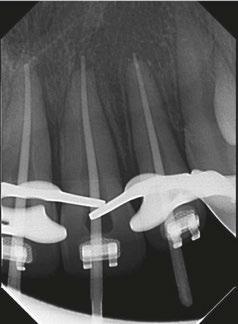

There are various factors that influence the size of such cavities, notably the anatomical location of the orifices and visualizing these orifices without tilting the mirror.12 This results in an access cavity that is widest occlusally and smallest at the level of the orifices.12,13 Hence the drawback of such access cavity design is that it requires the removal of healthy tooth structure, specifically the pericervical dentin — the dentin present 4 mm above and 6 mm below the crestal bone which helps to distribute any forces placed on the tooth (Figure 1).14 This access design, known as Traditional Endodontic Cavity (TEC) is presently being questioned, giving rise to various access designs emphasizing the preservation of this pericervical dentin.14,15

The increasing popularity of magnification, illumination, and CBCT technology, along with the goal to preserve pericervical dentin, gave rise to a series of new endodontic access cavities. These include conservative, ultra conservative (ninja), truss, guided, caries-oriented, and restorative access cavities.

Truss Access Cavity (Figure

2C)

In the discussion of smaller access cavities with the aim of preserving pericervical dentin, we include the Truss Access Cavity. This design yields separate access cavities on the occlusal surface, aligned with the corresponding canals, to expose the orifices and leaving the truss of dentin intact in between.19